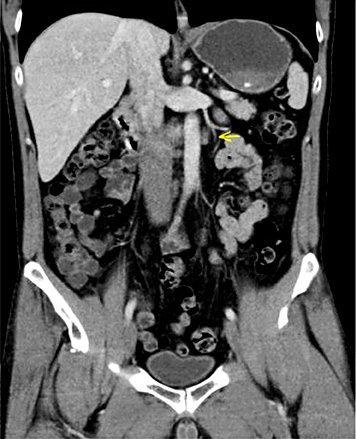

5th patient: this 23-year-old man underwent orchiectomy for marker-negative testicular seminoma at another institution. CT revealed intrathoracic nodules suspicious for mediastinal lymph node metastases. Accordingly, 4 cycles of BEP chemotherapy were administered. Restaging revealed unchanged mediastinal lymphadenopathy (Fig. 4). Then, the patient was referred to our institution for further management. Thorough pulmonological examination including transbronchial biopsy disclosed sarcoidosis-like lymphadenopathy, and thus metastatic disease was excluded. In view of these results, it must retrospectively be assumed that this patient had sarcoidosis synchronously with seminoma rather than having metastatic disease. Accordingly, the serum miR371a-3p level was RQ = 0.0 at the time of re-staging after chemotherapy. Unfortunately, no miR-levels were measured at the time of first presentation. Although speculative, one would assume that miR371a-3p levels had probably been low after orchiectomy for seminoma because the mediastinal lymphadenopathy had not changed ever since. By retrospective consideration, the normal marker level would have indicated the absence of metastases at the outset and accordingly, the patient could have been spared unwarranted chemotherapy and excessive diagnostic procedures apart from emotional distress from extended treatment.

Chest CT of patient #5 after 4 cycles of cisplatin-based chemotherapy: hilar lymphadenopathy. Transbronchial biopsy revealed sarcoidosis.